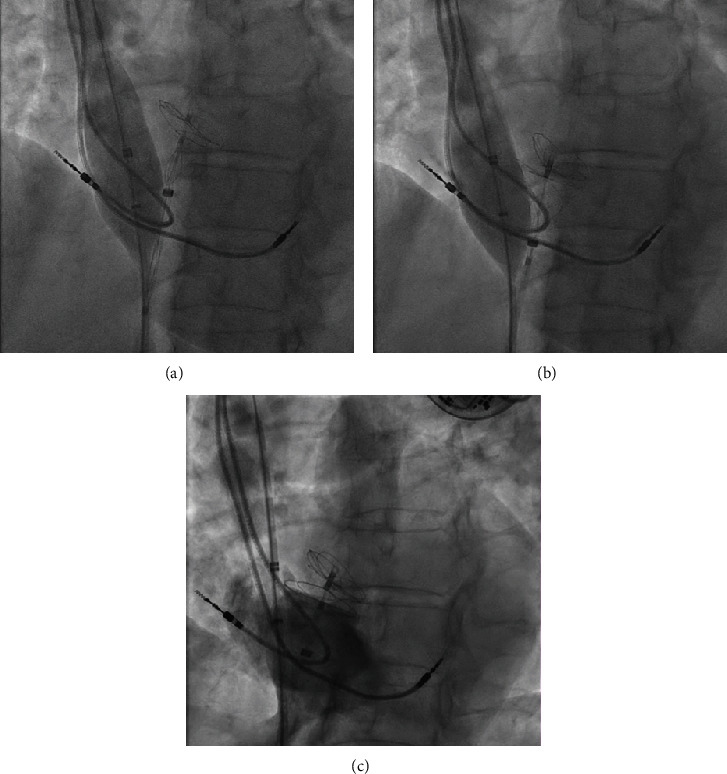

我们为您介绍一例可能因卵圆孔栓塞(PFO)引起的短暂性缺血性发作(TIA)患者。她的病史包括二度心脏传导阻滞 Mobitz II,表现为反复晕厥,曾接受双腔起搏器治疗。在 PFO 介入封堵术中,我们注意到心房起搏器导线被夹在右侧封堵器圆盘和房间隔之间。我们使用一个 24 毫米大小的球囊成功地将导联移至一侧,随后将右侧封堵器盘开发到正确位置。总之,使用尺寸调整球囊可以防止起搏器导联夹在 PFO 闭塞盘和房间隔之间。

We present a case of a patient with a transient ischaemic attack (TIA) likely due to paradoxical embolism through a patent foramen ovale (PFO). Her medical history included 2nd-degree heart block Mobitz II, which manifested with recurrent syncopes and was treated with a dual chamber pacemaker. During the interventional PFO closure procedure, we noted entrapment of the atrial pacemaker lead between the right-sided occluder disc and the interatrial septum. We were able to successfully move the lead aside using a 24 mm sizing balloon and subsequently developed the right-sided occluder disc in the correct position. In conclusion, pacemaker-lead entrapment between a PFO occluder disc and the interatrial septum can be prevented using a sizing balloon.